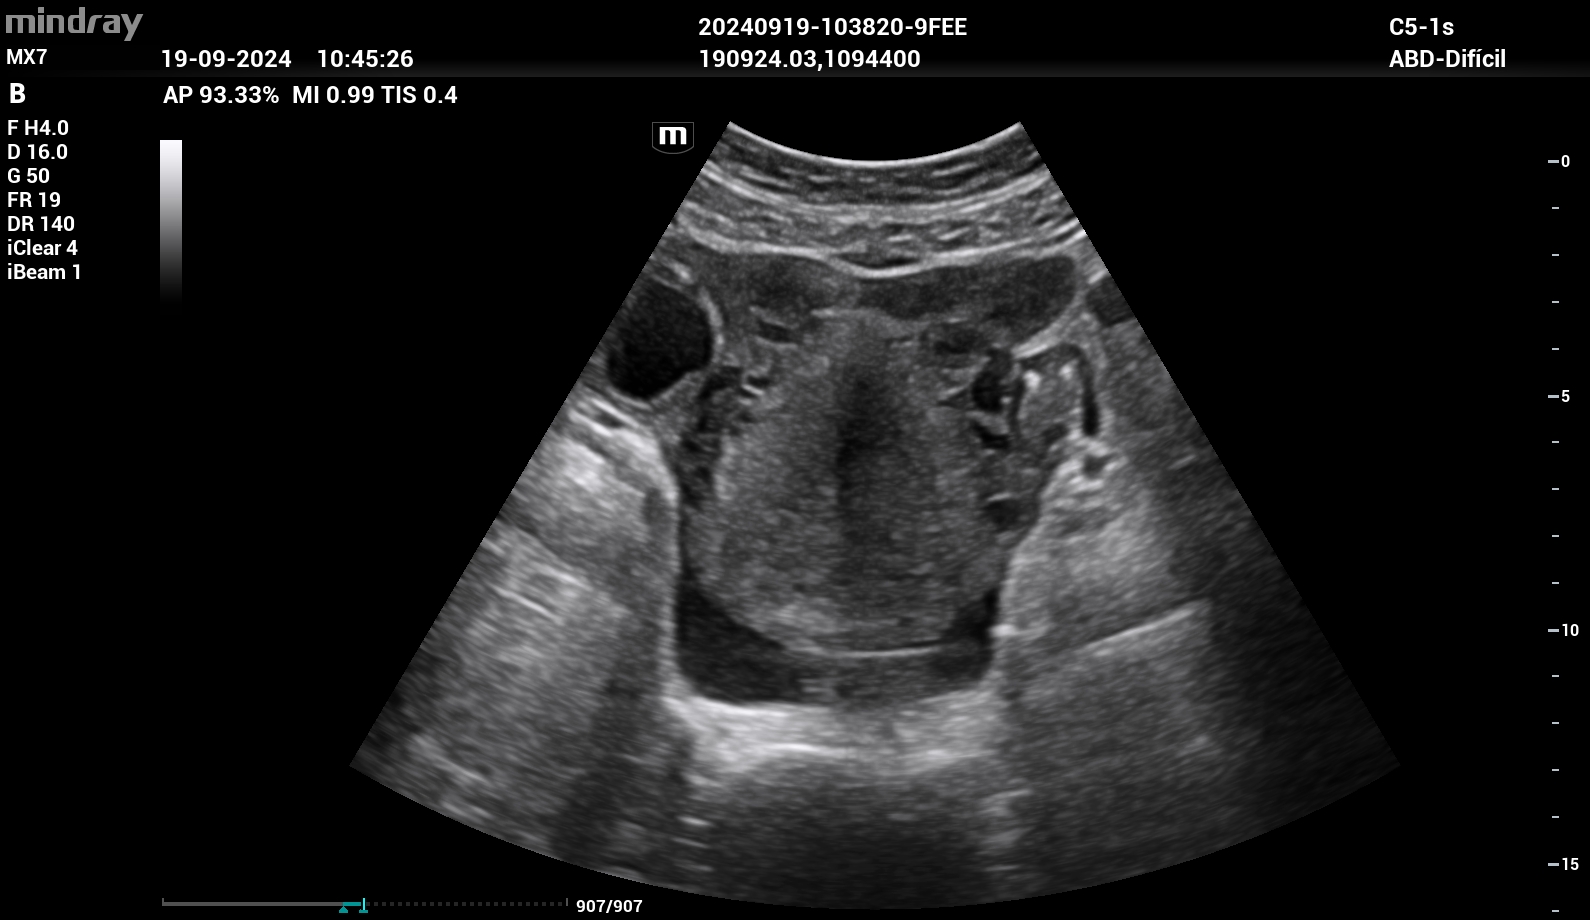

Se realizó ecografía clínica donde se objetivó líquido libre intraabdominal en espacio de Douglas. Útero en anteversión sin vesícula gestacional en interior. En región paraovárica derecha presentaba imagen ecomixta de 40 x 31 mm sugestiva de embarazo ectópico.